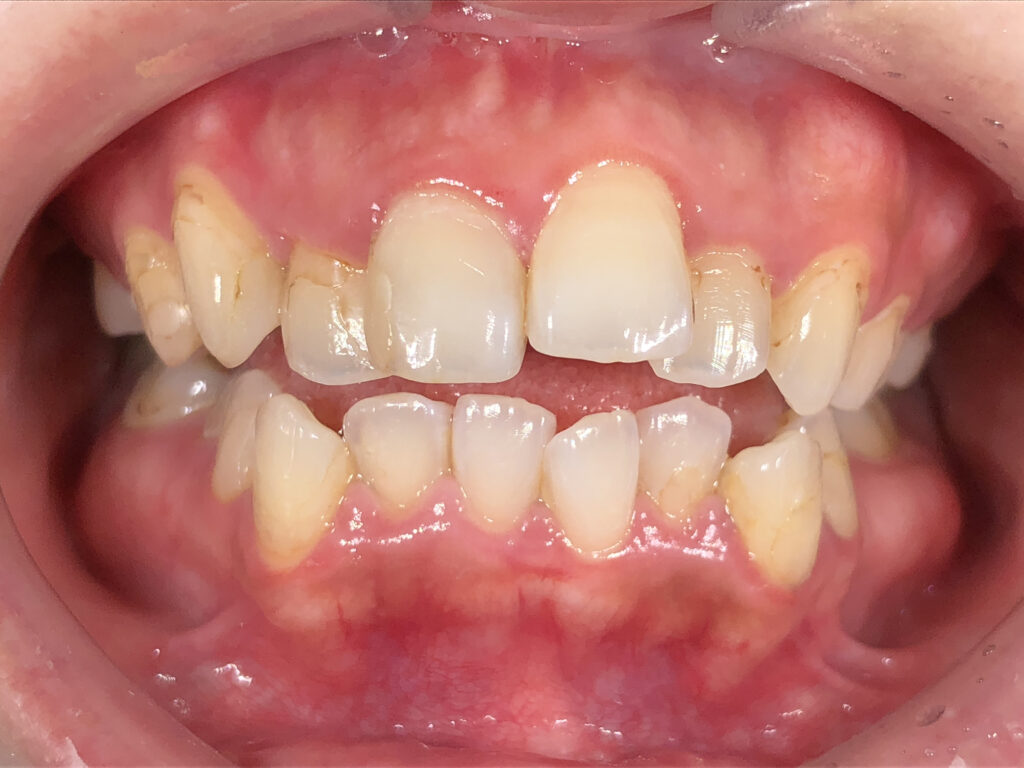

正面

治療前